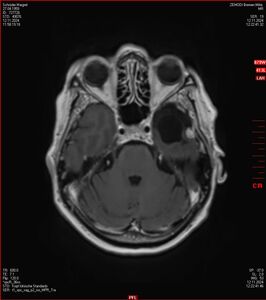

Zum Vergleich nun auch die Bilder vom 1.12.2023:

Ich denke, in den letzen 12 Monaten sind da ein paar Rezidive gewachsen,  vor 12 Monaten waren sie auch schon zu erkennen - vorher noch nicht. Nun hoffe ich auf den Rat des Spezialisten. Hoffendlich kann man etwas machen.